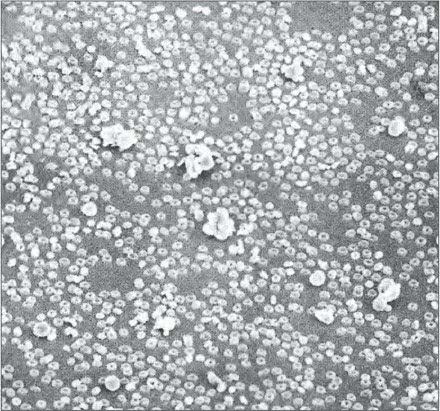

Макрофотография клеток крови человека. Клетки, напоминающие пончики, – это красные кровяные тельца (эритроциты), переносящие кислород. Более крупные комки – белые кровяные тельца, которые уничтожают чужеродные микроорганизмы.

Электронные микрофотографии клеток крови человека (с последовательным увеличением). На верхнем снимке большинство клеток – красные кровяные тельца. Клетка, которая занимает весь нижний снимок, это B-лимфоцит, внутрь которого мы заглянем на следующей странице. Его диаметр – около одной десятитысячной сантиметра.